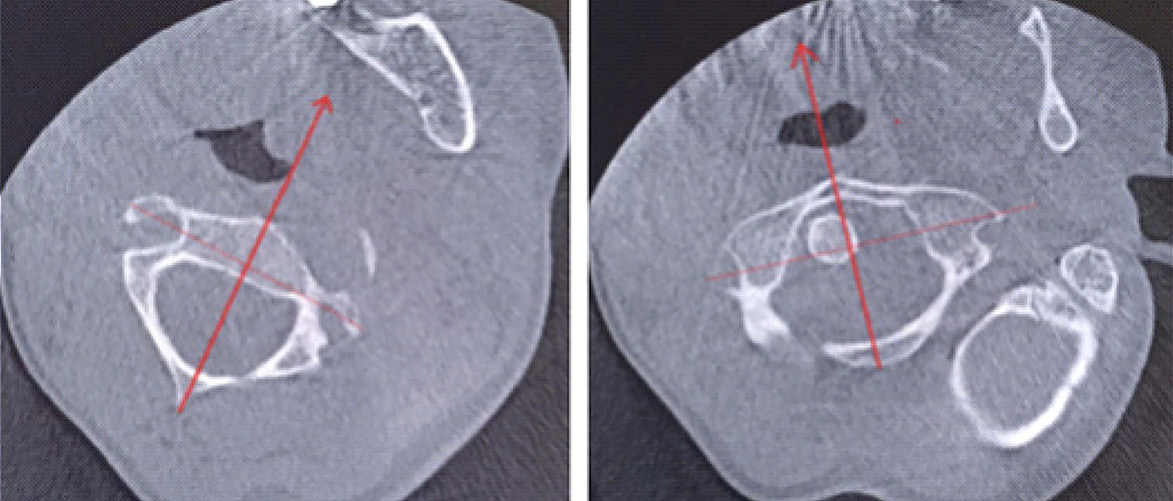

Для уточнения характера выявленных изменений в ручном режиме с помощью программы Adobe Photoshop© выполнено наложение аксиальных срезов 1-го и 2-го шейных позвонков, полученных по отдельности, с созданием единого изображения с возможностью комплексной оценки взаимоотношений изучаемых сегментов (рис. 2). При анализе смоделированного изображения обнаружено, что ротация атланта составляет 35° вправо (рис. 3). Суставные поверхности латерального атлантоаксиального сустава справа совпадают, а слева –суставная поверхность атланта смещена кпереди, что соответствует ротационному подвывиху типа II по классификации J. W. Fielding и R. J. Hawkins [8].

Рис. 2. Конусно-лучевая компьютерная томография краниовертебральной области. Аксиальные срезы на уровне аксиса (А) и на уровне атланта (Б). Стрелками обозначены передне-задние оси позвонков

Рис. 3. Наложение изображений А и Б, представленных на рис. 2. Определение угла ротации атланта